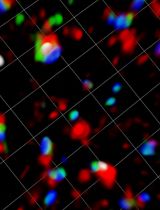

Immunotherapy has demonstrated great therapeutic potential by activating the immune system to fight cancer. However, little is known about the specific dynamics of interactions that occur between tumor and immune cells. In this protocol we describe a novel method to visualize the interaction of tumor and immune cells in the lung of live mice, which can be applied to other organs. In this protocol fluorescent-labeled tumor cells are transferred to recipient mice expressing fluorescently tagged immune cells. Tumor-immune cell interactions in the lung are then imaged by confocal or two photon microscopy. Analysis of tumor interactions with immune cells using this protocol should aid in a better understanding of the importance of these interactions and their role in developing immunotherapies.

A number of immunotherapies have demonstrated great promise in treating cancer. Understanding the spatial temporal resolution of how these tumor-immune interactions occur is important for enhancing and developing new immunotherapies. In this protocol we describe a novel method to directly visualize tumor-immune cell interactions in vivo in mouse lung. This protocol is initially described in our work examining the interactions of patrolling monocytes and tumor cells in the mouse lung (Hanna et al., 2015). This fluorescent microscopy protocol uses the vacuum imaging ring to stabilize and image the lung, which was initially described by Looney and colleagues (Thornton et al., 2012). In this protocol fluorescent-labeled tumor cells are transferred to recipient mice expressing fluorescently tagged immune cells. Tumor-immune cell interactions in the lung are then imaged by confocal or two photon fluorescent microscopy using the vacuum imaging ring. This protocol allows for the addition of other immune cell markers by intravenous (IV) injection of fluorescently labeled antibodies, and is adaptable to image tumor-immune cell interactions in other organs. Quantitative information such as the localization, engulfment of tumor material, timing, speed and frequency of these immune cell interactions can be collected using this protocol. This protocol should aid in helping to better understand the specific immune-tumor cell interactions that are important to developing better immunotherapies in the future.